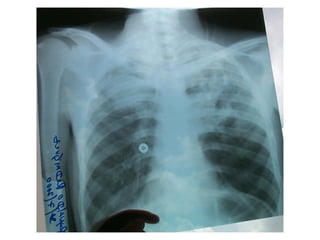

Question 10 44yo with 3 week h/o fever, purulent cough and wt loss SZ d/o s/p seizure 1 month ago CXR with 2.5cm cavity in superior segment RLL with A/F level (+) ppd

What is the most appropriate therapeutic step? A.  Culture sputum for anaerobic bacteria and begin treatment with clindamycin B.  Send sputum for AFB stain and culture and begin treatment with INH, RIF, PZA and ETB C.  Begin treatment with metronidazole and schedule bronchoscopy Send sputum for gram stain and AFB and treat empirically with piperacillin/tazobactam

Question 10 Send sputum for gram stain and AFD and treat empirically with piperacillin/tazobactam  Identify the clinical presentation of a lung abscess and select appropriate therapy.

Question 10 44yowith 3 week h/o fever, purulent cough and wt loss SZ d/o s/p seizure 1 month ago CXR with 2.5cm cavity in superior segment RLL with A/F level (+) ppd

What is themost appropriate therapeutic step? A. Culture sputum for anaerobic bacteria and begin treatment with clindamycin B. Send sputum for AFB stain and culture and begin treatment with INH, RIF, PZA and ETB C. Begin treatment with metronidazole and schedule bronchoscopy Send sputum for gram stain and AFB and treat empirically with piperacillin/tazobactam

Question 10 Sendsputum for gram stain and AFD and treat empirically with piperacillin/tazobactam Identify the clinical presentation of a lung abscess and select appropriate therapy.